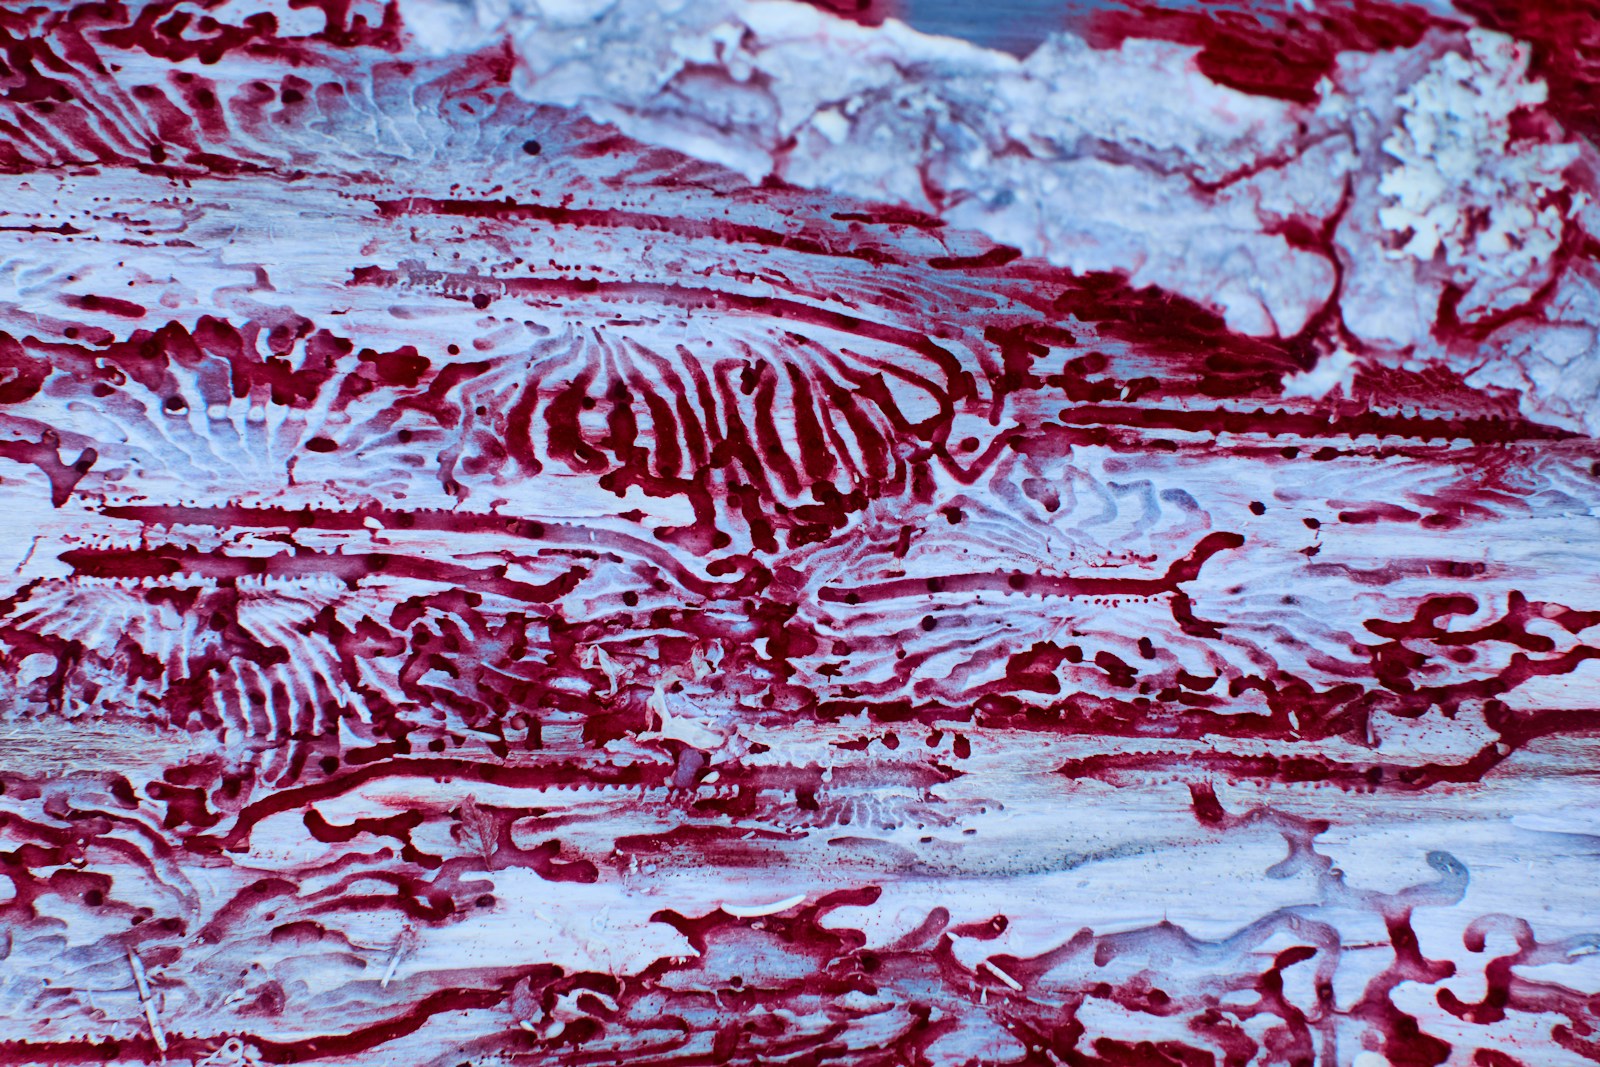

Stem cells are important in the maintenance and repair of many tissues all along the life span. It is the case in skeletal muscle, which presents high plasticity and regenerative properties to keep constant physiological parameters (homeostasis). Normal skeletal muscle mobilizes tissue-associated endogenous stem cells, mainly satellite cells, to repair damaged myofibers. Indeed, muscle stem cells sustain regeneration that is crucial for muscle homeostasis, as well as the self-renewal mechanisms that maintain their pool constant.

A key issue we address is the tissue environment in which muscle stem cells are activated. Environment plays important roles in the behavior of muscle stem cells and myogenic cells, although the mechanisms are poorly unknown. Various cell types in the vicinity of stem cells communicate with each other to correctly drive regeneration. We explore the roles of immune cells (inflammation), endothelial and peri-endothelial cells (angiogenesis) and interstitial cells (fibrosis) on myogenic cell fate in normal healthy regenerating muscle and during muscular dystrophies. Indeed, myopathies are characterized by the alteration in the environment of muscle stem cells, such as the presence of chronic inflammation and fibrosis, which are detrimental for both tissue repair and cell therapies.